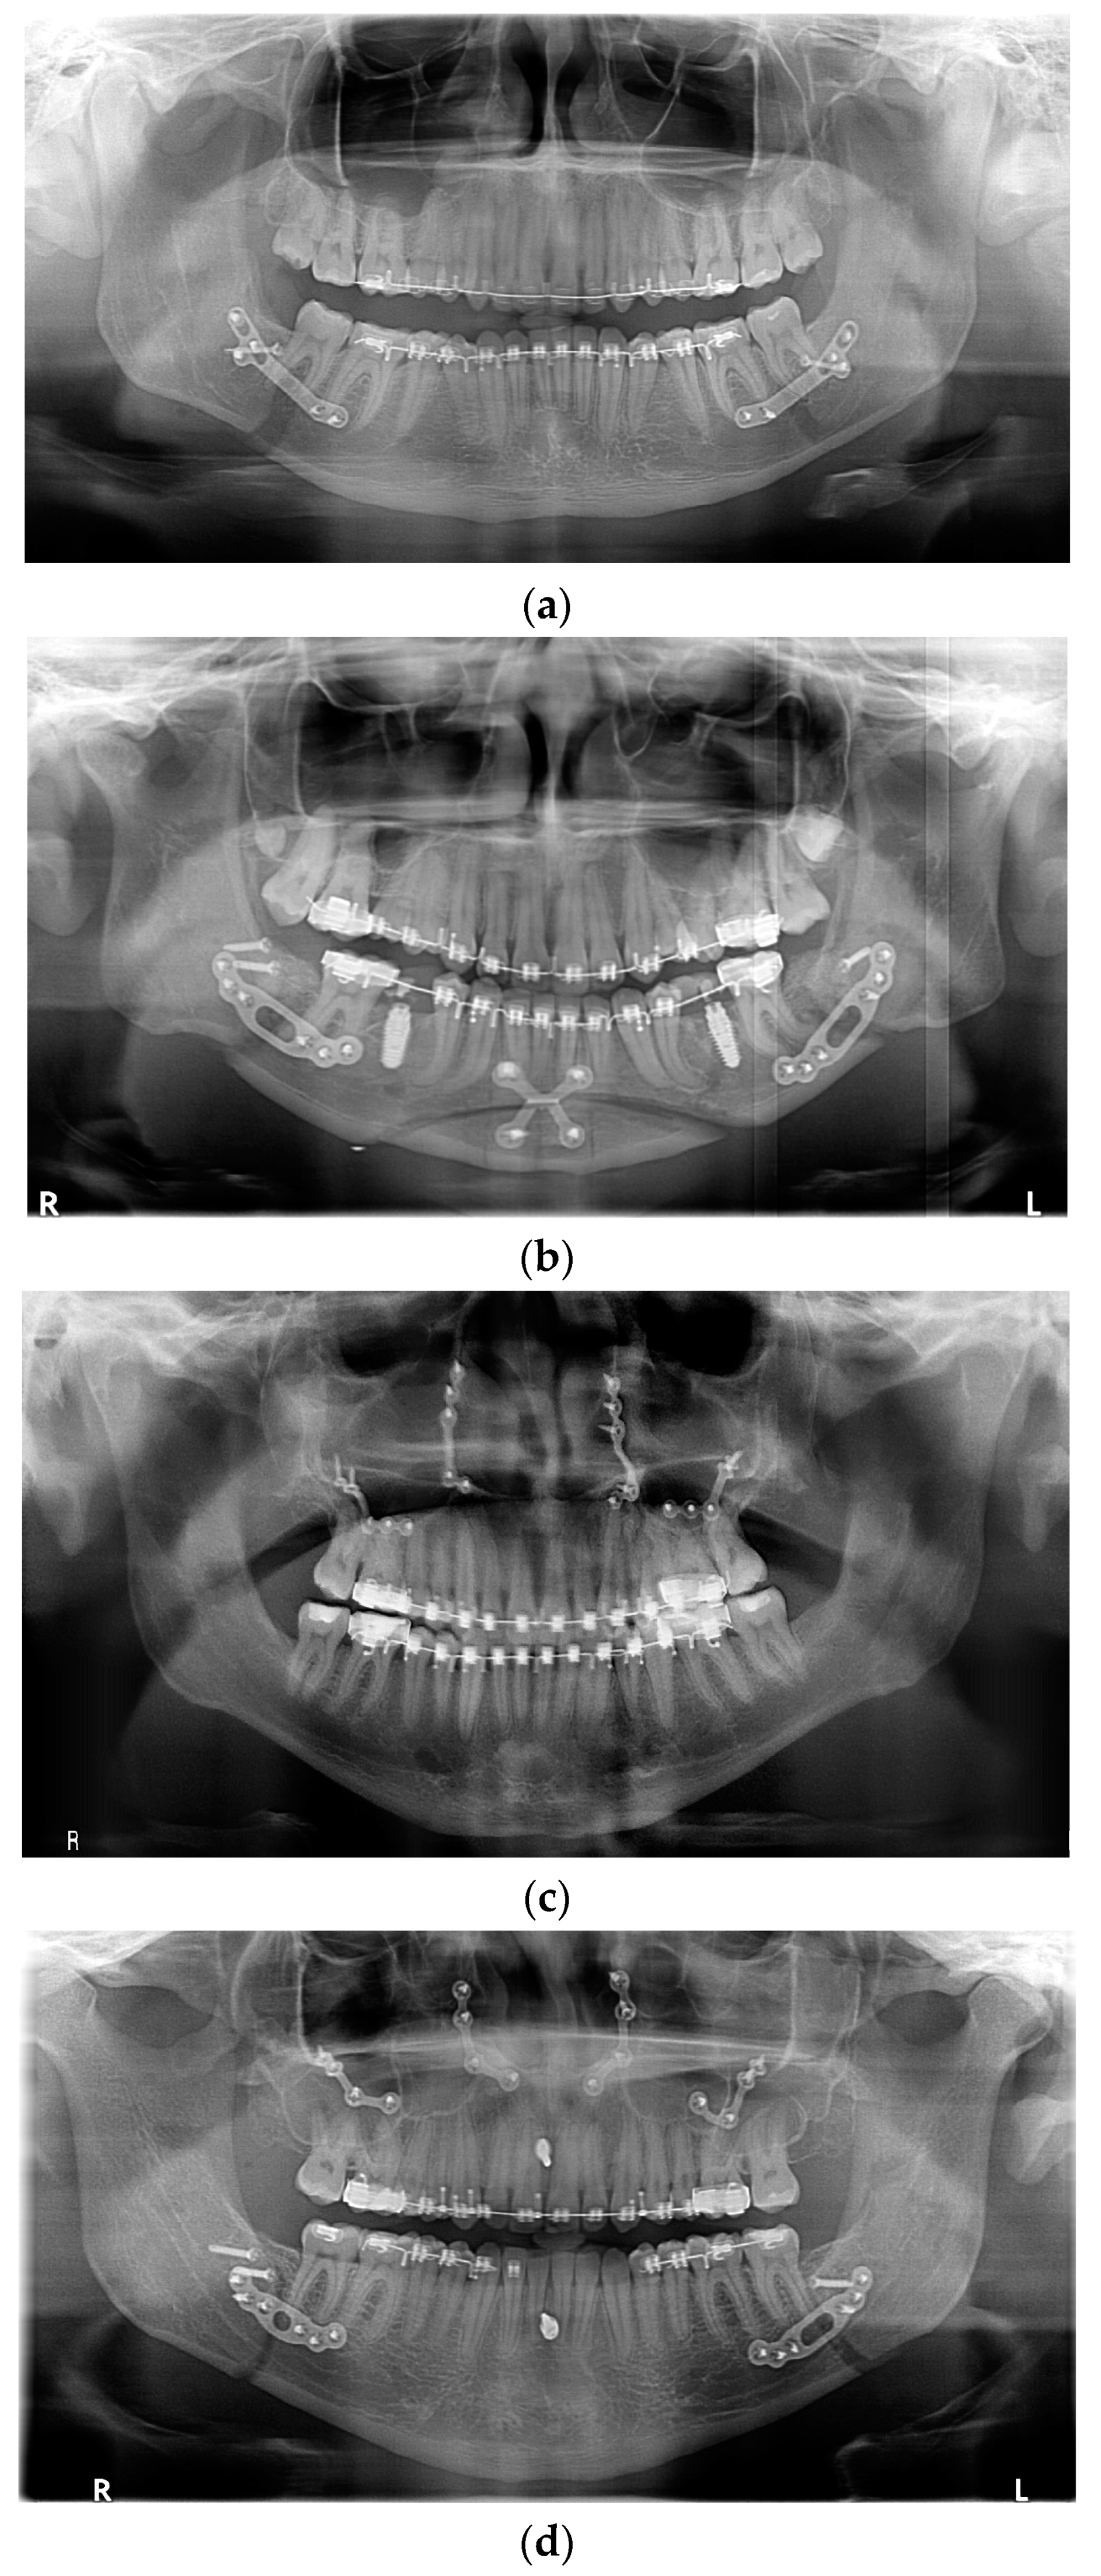

All fixation hardware used in orthognathic procedures was made of titanium (Figure 1).

Figure 1.

Panoramic X-ray with fixation hardware: (a) after BSSO; (b) after BSSO and genioplasty; (c) after Le Fort I osteotomy; (d) after bimax; (e) after bimax with maxillary segmentation and genioplasty.

In the case of sagittal mandibular ramus osteotomy, the typical way to fix the osteotomy fragments was to use one bicortical screw as well as a single plate and monocortical screws on both the right and left side. In a few selected cases, only three bicortical screws were used without a plate, the use of a bicortical screw was abandoned and the fragments were provided fixation using only one plate, and monocortical screws or more than one bicortical screw and a plate were used. Each time it was dictated by individual anatomical and mid-operative conditions. All fixation hardware in the mandible was made with screws that required drilling and were made through an intraoral approach.

In Le Fort I maxillary osteotomy, the osteotomy fragments were typically fixed using 4 plates (most commonly in the shape of the letter “L”; for maxillary segmentation “Y” plates were used) and an appropriate number of monocortical screws. Screws that do not require drilling, i.e., self-drilling screws, were used. In selected situations dictated by anatomical conditions, customized solutions were used in the form of an additional plate, a non-standard shaped plate, or a reduced number of screws.

For genioplasty, dedicated plates with a bridge of appropriate length or two plates bent by the operator according to the planned bone movement were used together with monocortical screws.